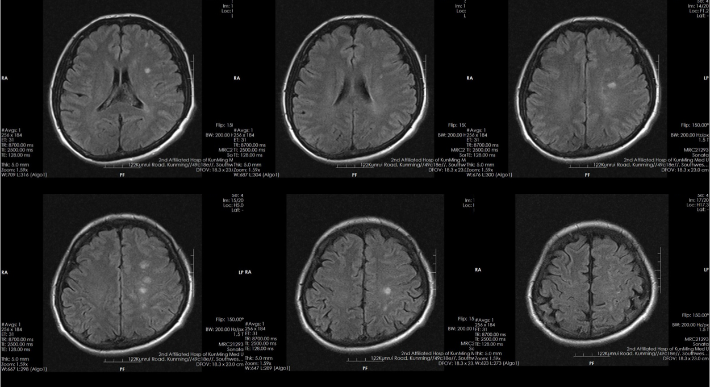

8月前起病时头颅磁共振

CTP

✔本例患者为症状性颅内动脉狭窄,已发生脑梗死(交界区点片状梗死,考虑为低灌注所致)

--CTP有低灌表现

--DSA显示左侧颈内虹吸段狭窄约72%。前交通开放,右侧大脑前动脉通过前交通动脉向左侧大脑前动脉、大脑中动脉供血区有代偿供血。

--双抗治疗下仍有缺血症状发作。评估有手术指征,无手术禁忌。